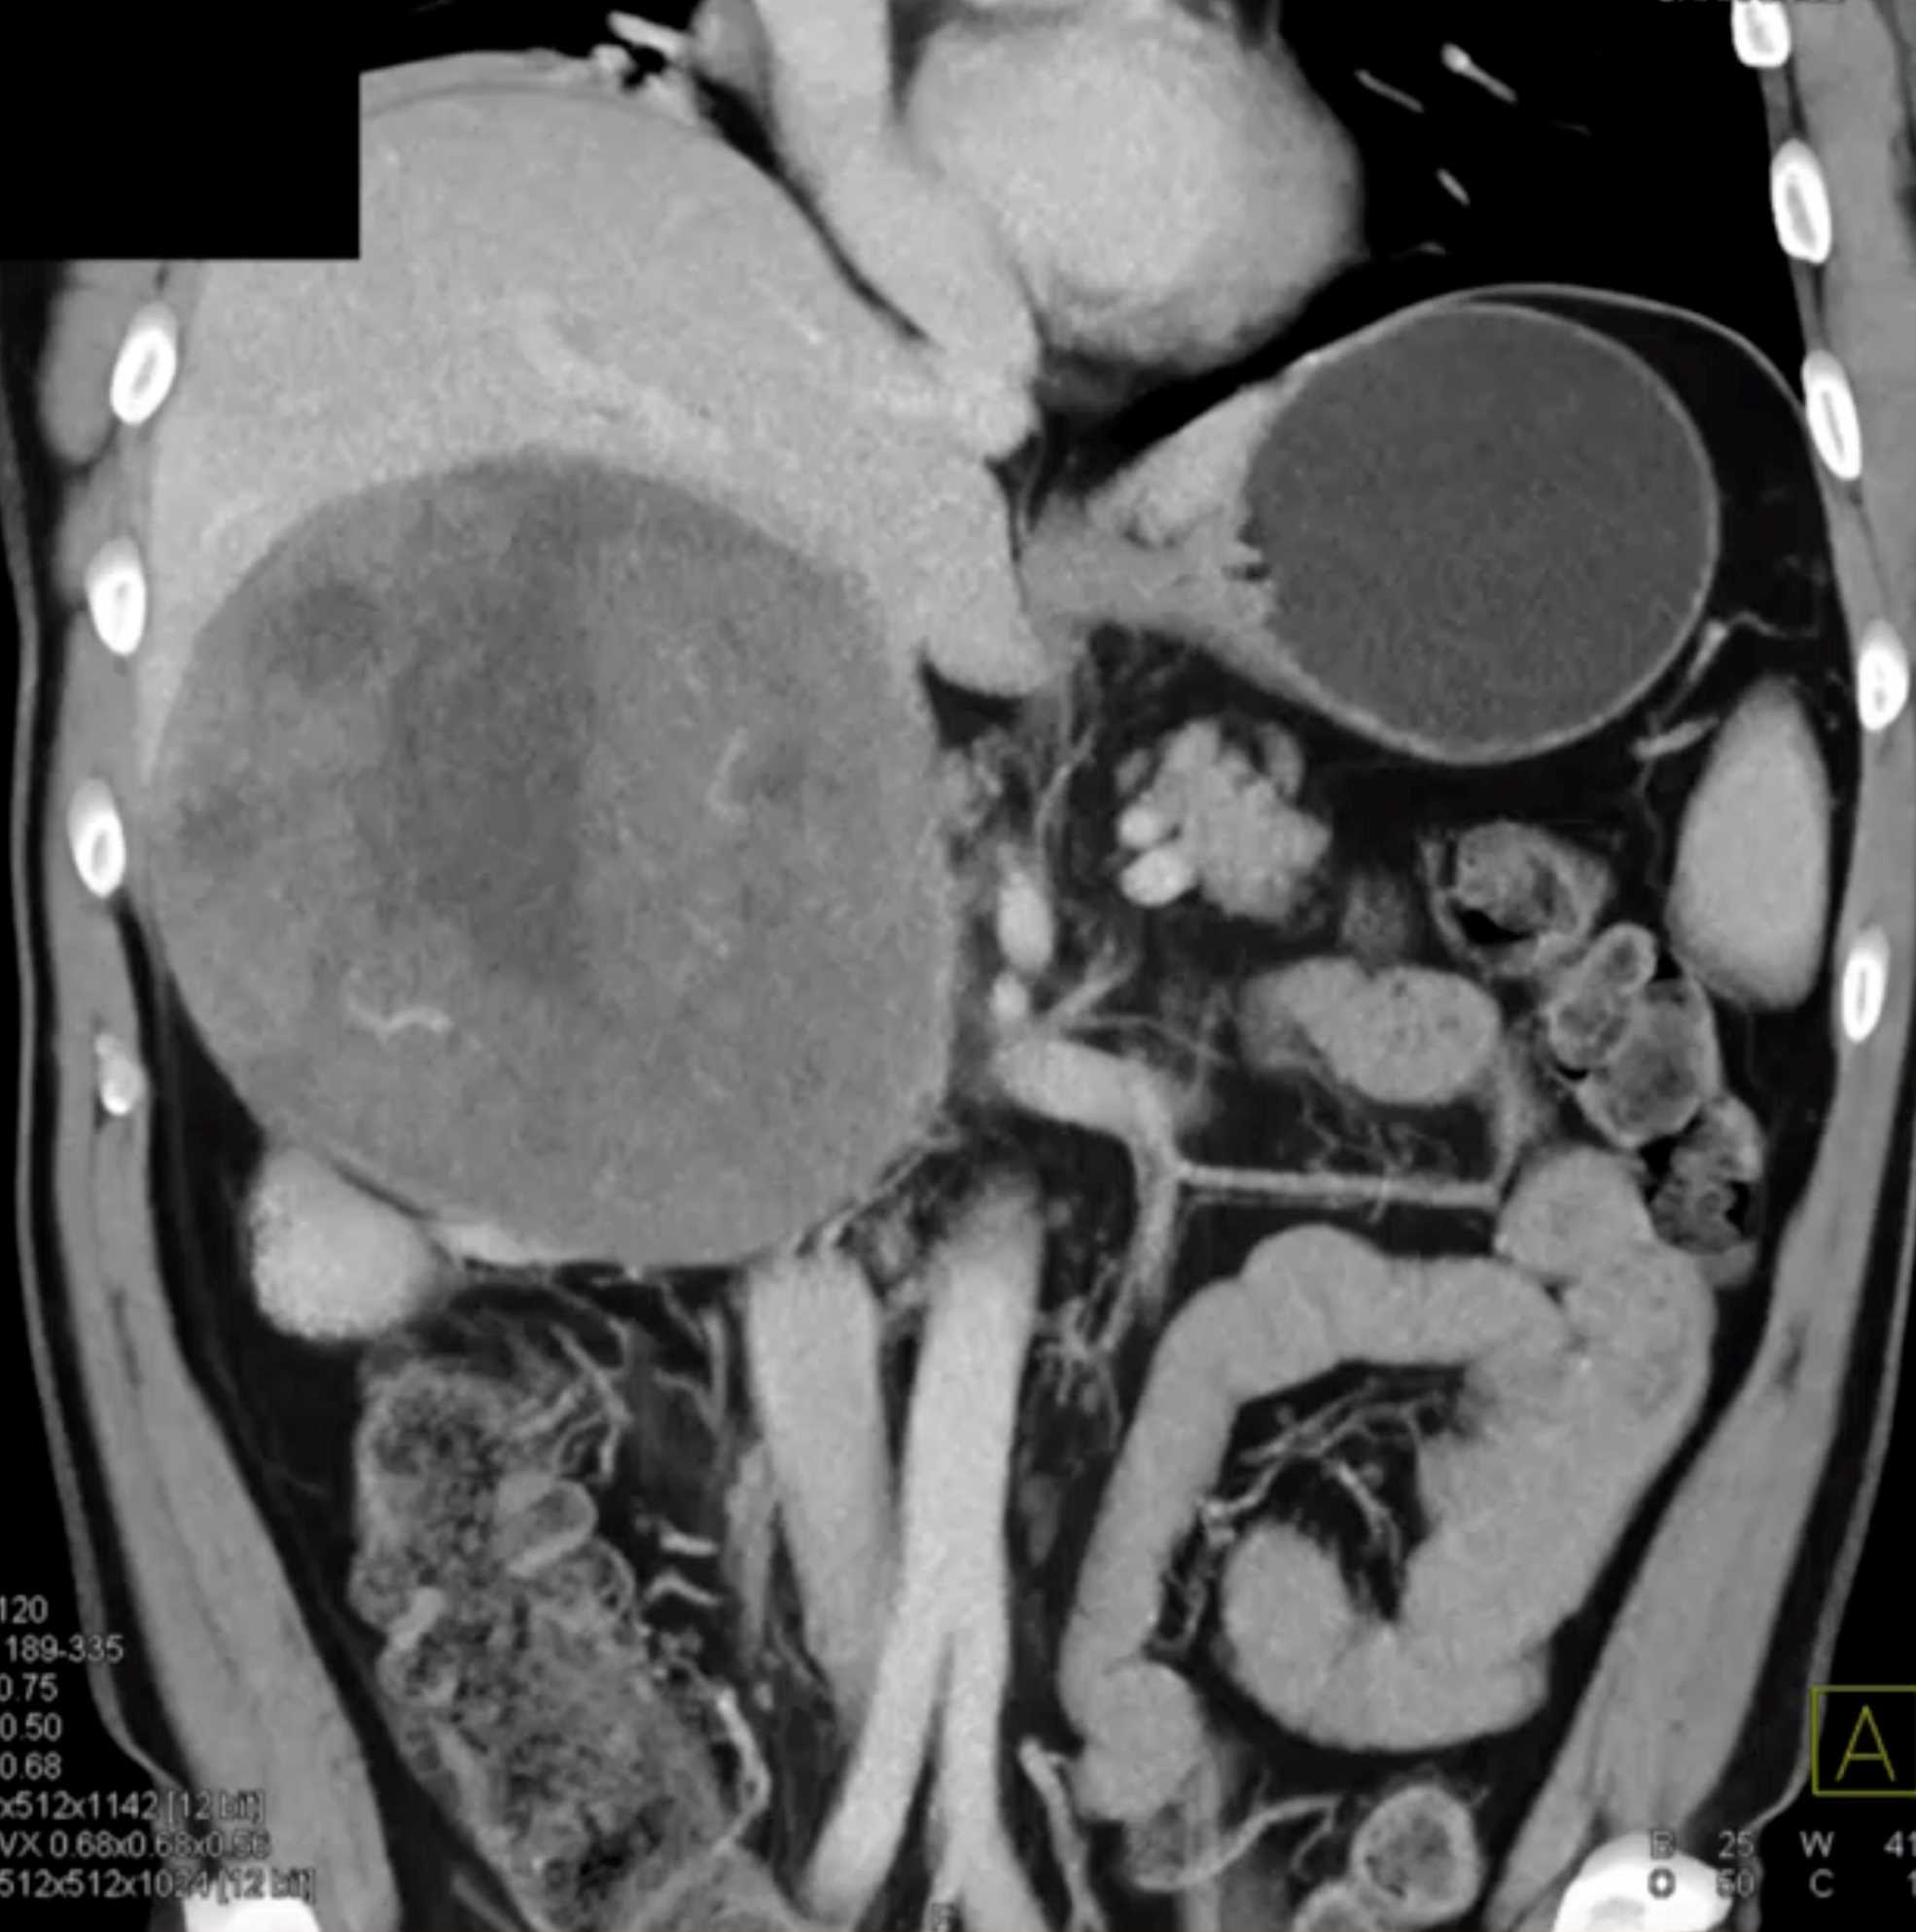

Left Adrenal Metastases from Renal Cell Carcinoma